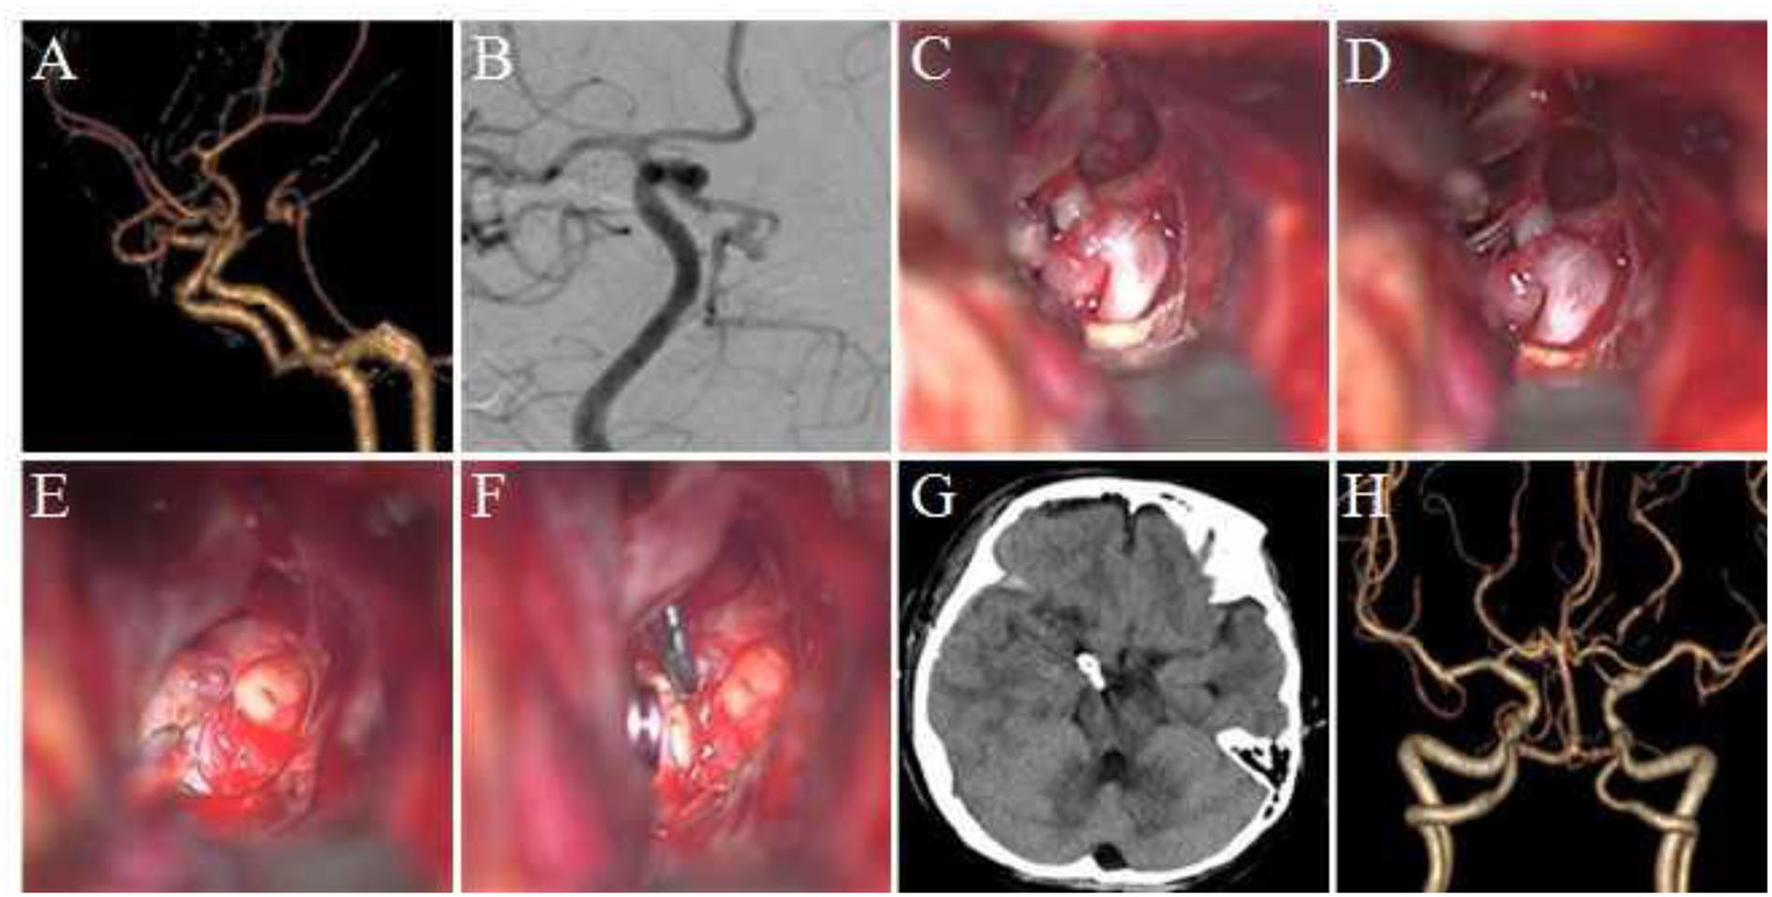

FIGURE 2

Figure 2. Clipping of the aneurysm at the P1–P2 bifurcation of the posterior cerebral artery via the Dolenc approach. (A) Preoperative head CT revealed subarachnoid hemorrhage. (B) DSA revealed the tumor at the P1–P2 bifurcation of the right posterior cerebral artery. (C) The aneurysm was exposed during the surgery; the wall of the apical aneurysm was thin, and adhesion was observed between the aneurysm and temporal lobe. (D) The aneurysm was clipped parallel to the parent artery during the surgery. (E) Re-examination using head CT within 12 h after surgery. (F) Postoperative CTA revealed no development of aneurysm and no vascular damage.